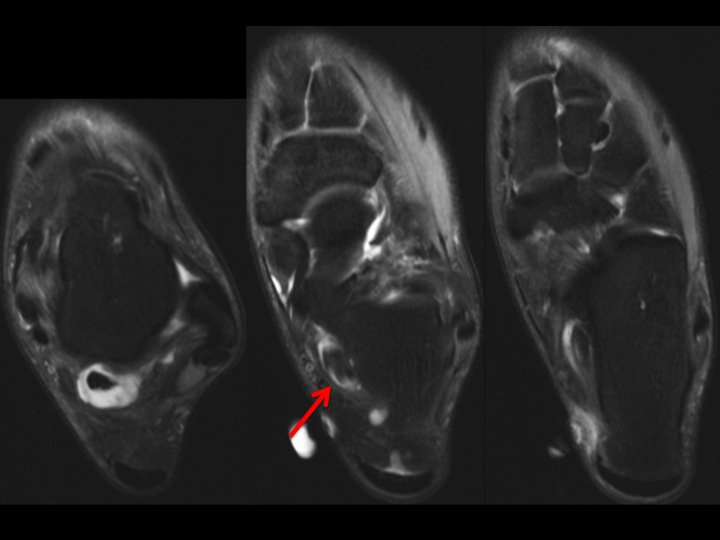

Figure 2 for case FHL partial tear and tenosynovitis

Figure 2

There is a low grade partial tear near the level of the subtalar joint with moderate tenosynovitis. Ive seen relatively few FHL tears, and not in this location.

FHL partial tear and tenosynovitis